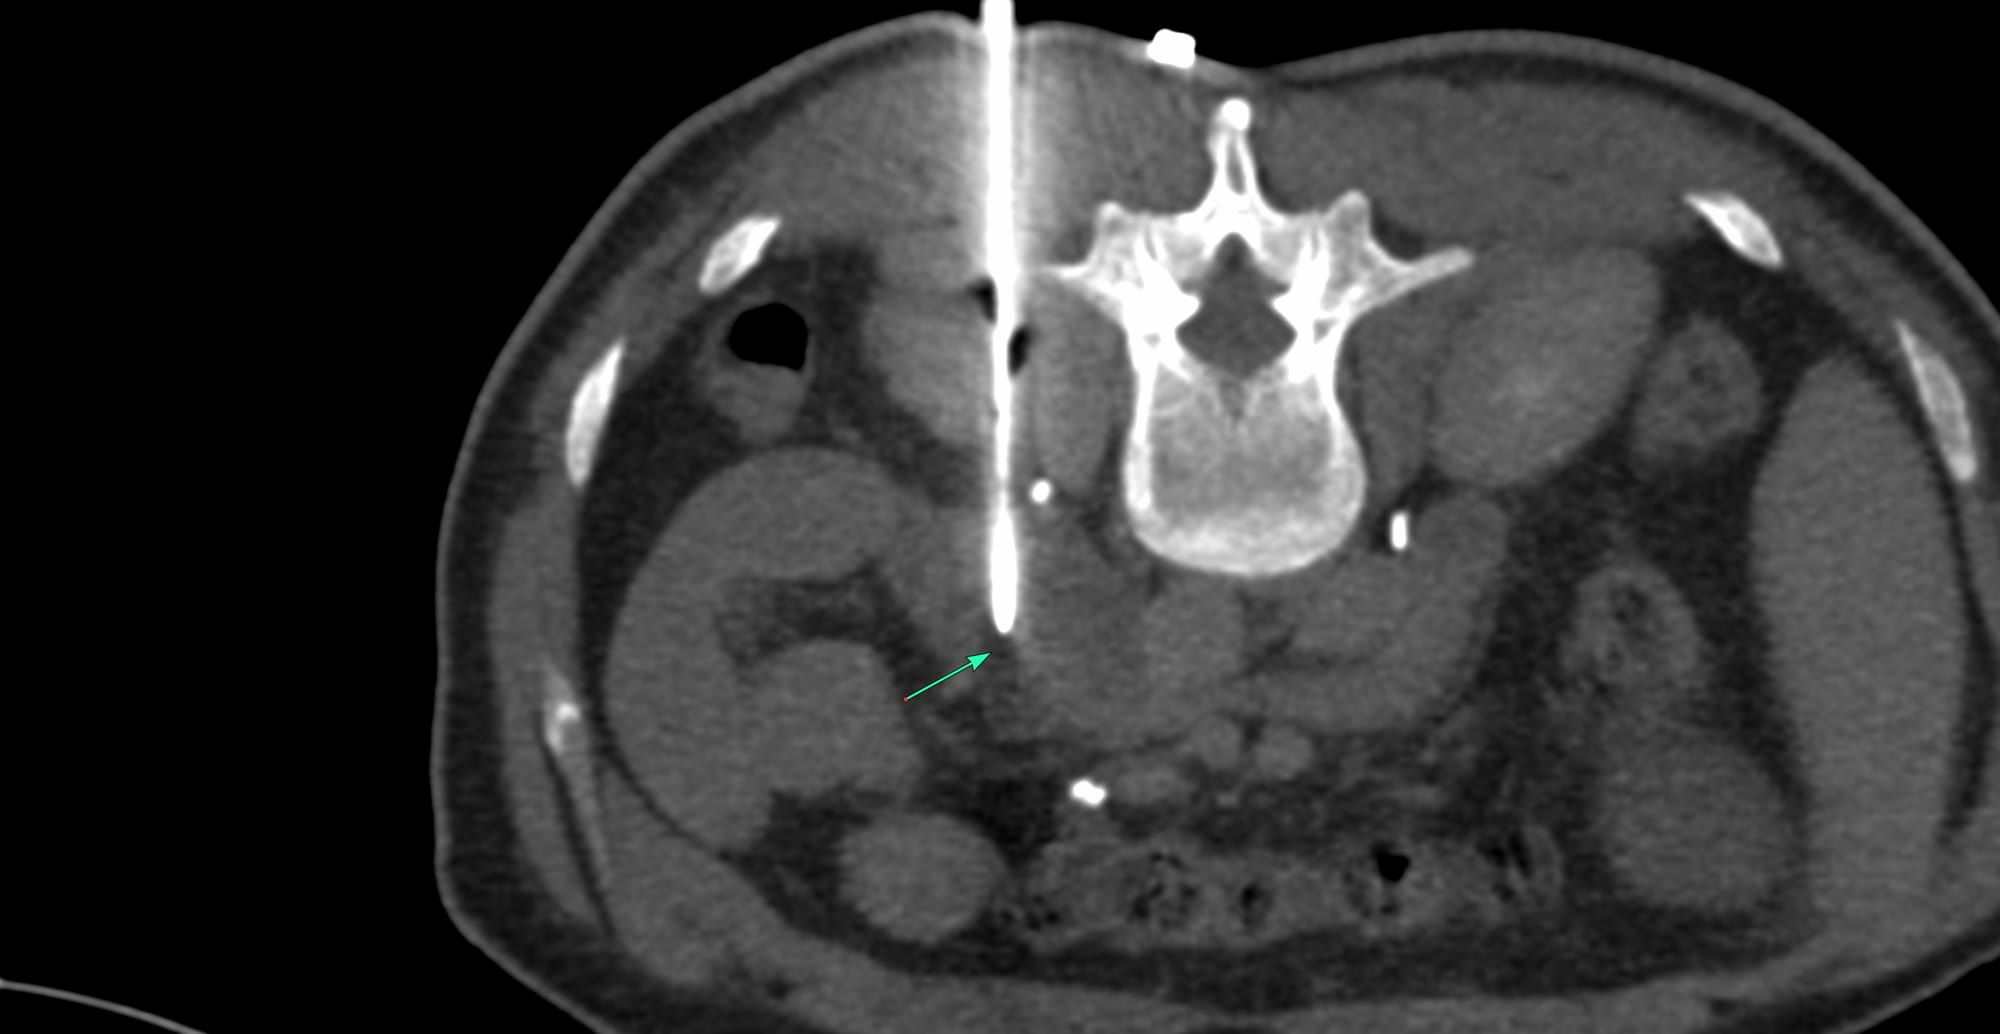

Case of the Day 106 - 2025 09 22 - Retroperitoneal Posterior Parapsoas Approach - Macrocystic Lymphatic Malformation Aspiration

Bhavin Jankharia - 02 October 2025